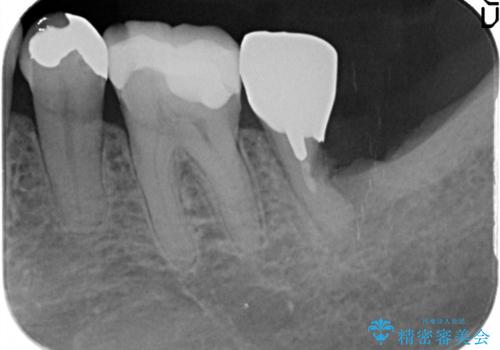

- 半分残していた奥歯の虫歯の状態が良くない為、抜歯をしてインプラントをしました。

向かい合わせの歯の治療も、神経の治療からセラミックのかぶせ物まで行っています。

- 69.4万円 内訳:左下7(ストローマンインプラント24.2万円 インプラント用仮歯2.2万円 骨増成5.5万円 カスタムアバットメント11万円 FGG(遊離歯肉移植術)11万円 静脈内鎮静5.5万円)費用は治療当時の料金となります

他の歯の治療もあり治療に時間をかけることが問題なかった点、また、審美領域ではない点、患者様が時間をかけてもいいのでお手入れしやすく長持ちするインプラントを希望していたことから2回法を選択しております。一回法のメリットは今回は特にありませんでした。患者様のご希望もふまえ、無理せず抜歯後しっかり骨ができるのを待って、角化歯肉を増やすため歯肉移植も行いました。